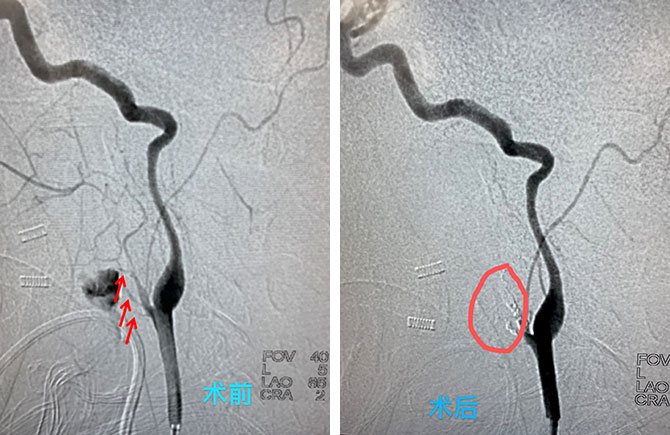

耳鼻喉科邱前辉主任向神经外科陈光忠主任发出了紧急会诊。在向周东主任和医务科报备拟行急危重症患者手术的同时,神经外科团队分头行动,查看病人、同时向介入室发出开通绿色抢救通道申请,麻醉科积极配合,孙强主任亲临介入室指导。神经外科团队快速为患者行股动脉穿刺、行目标侧血管造影,明确出血部位。但出血部位位置低,靠近重要血管颈内动脉,需快速实施精准栓塞治疗,即要堵塞出血点,又要保护好重要血管。神经外科团队在微导管微导丝导引下快速准确到位,依次封堵多个出血点。

这时,患者床旁血色素监测持续下降,最低到1g/L,命悬一线,生死时速。在各学科团队的共同努力下,一小时内完成了全麻下脑血管造影及颈部出血血管堵塞止血。在继续输血及血色素呈现稳定上升趋势后,患者被送到EICU继续救治,患者当晚即神志清醒,生命体征稳定,四肢可活动,术后4小时复查血常规:血色素升至68g/L。患者最终转危为安。